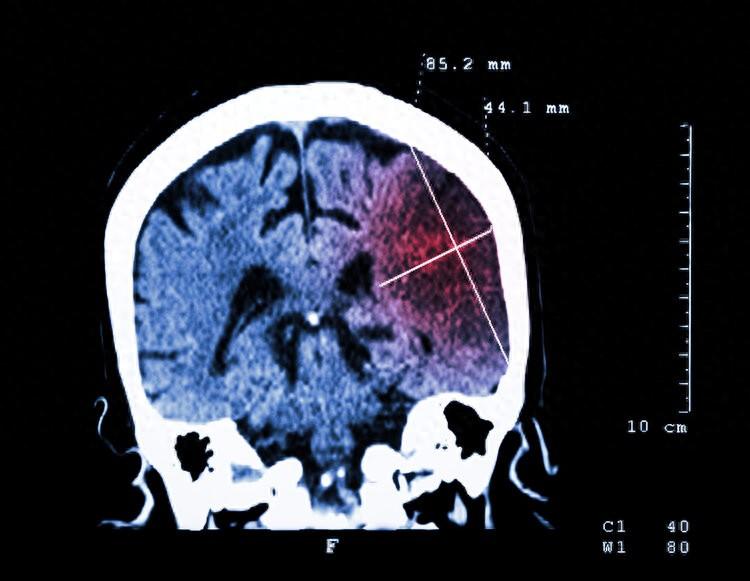

可過了一段時間後,眼睛不但沒有好轉,反而越來越嚴重了,便趕緊讓兒子帶着到了醫院檢查。眼科醫生建議劉叔叔到神經科去看診,經頭顱核磁共振檢查發現是腦梗引發的視覺模糊。

由於劉叔叔右側腦部的腦梗破壞了視覺形成通路,從而引發了視物模糊,好在經過醫院的積極治療,劉叔叔左眼視力在不斷恢復。

山東省中醫院康復科主治醫師任碩刊文指出:有些腦梗患者病竈小、發病緩慢時,可能並沒有偏癱等一些感覺障礙,反而會以視覺障礙而就診,因此眼睛上出現的某些異常表現,可能是腦梗的信號。

尤其是當眼部出現以下4種異常時,一定要多留心。